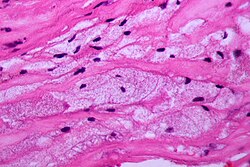

Schaumzellen bilden einen großen Teil aller bekannten arteriosklerotisch geschädigten, im Volksmund auch „verkalkt“ genannten Blutgefäße. Sie entstehen in den Schichten Intima und Media der Gefäßwände durch Fetteinlagerungen.

Schaumzellen werden häufig bereits bei Kindern und Jugendlichen beobachtet, dort ist ihre Entstehung jedoch meist nur vorübergehend (reversibel). Diese gelblich gelatinösen Fettschichten, die von Medizinern auch als fatty streaks bezeichnet werden, können 10 bis 50 % der Arterieninnenwände bedecken. Untersuchungen dieser Schädigungen (Läsionen) ergaben, dass sie sowohl aus fettbeladenen Makrophagen als auch fettbeladenen glatten Muskelzellen zusammengesetzt sind. Tumoröse Ansammlungen von Schaumzellen in der Haut werden Xanthome genannt.

Die normalerweise im Blut zirkulierenden Makrophagen gelangen in ihrer Vorform, als Monozyten, in die unteren Gefäßschichten durch Durchdringung der Endothelzellschicht. Dieser Vorgang wird durch chemotaktische Faktoren stimuliert. Erst in der Media (Subendothelium) erfolgt eine Änderung des Erscheinungsbildes der Monozyten und eine Differenzierung zu Makrophagen. Dort können die Makrophagen Lipide und Cholesterinester einlagern. Dies wiederum kann direkt zur Bildung von Schaumzellen führen.

Der Mechanismus der Entstehung von Schaumzellen aus glatten Muskelzellen und Makrophagen ist nur zum Teil aufgeklärt. Einig ist man sich über die Beteiligung von chemisch modifiziertem (oxidiertem) LDL, welches von den Makrophagen über Scavenger-Rezeptoren ungehemmt und konzentrationsunabhängig aufgenommen und gespeichert wird. Diese Scavenger-Rezeptoren finden sich auch in glatten Muskelzellen. Zu vermuten ist, dass Mechanismen, mit denen beide Zellarten eine Überladung mit Lipiden und Cholesterin verhindern könnten, außer Kraft gesetzt oder beeinträchtigt sind.